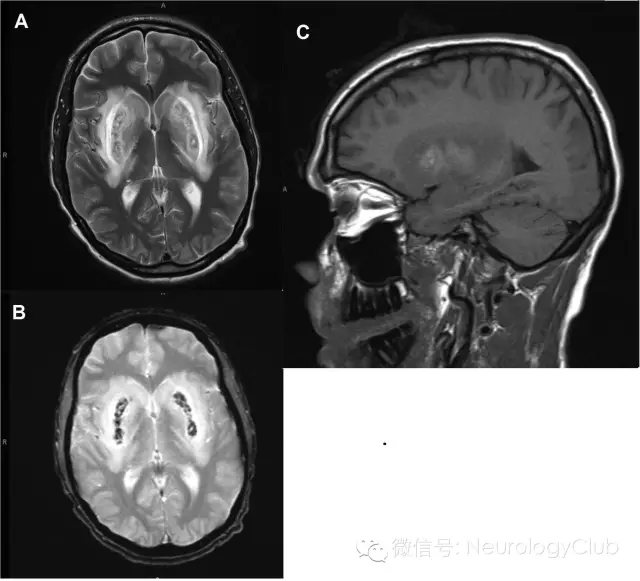

33岁男性,因逐渐加重的抑郁症状和新出现的意识障碍被家属送至急诊室,病程5天。先前有自杀未遂史,无其他疾病史,也并未服用任何药物。实验室检查提示代谢性酸中毒,阴离子间隙32mmol/L。血浆渗透压558mmol/kg,渗透压间隙268mmol/kg。肝酶轻度升高,天门冬氨酸氨基转移酶242U/L,丙氨酸氨基转移酶247U/L。患者意识障碍迅速恶化,予气管插管转至重症监护室。头颅CT正常。头颅MRI提示双侧壳核病变。

(图:A:T2WI;B:T2梯度回波序列;C:T1WI)